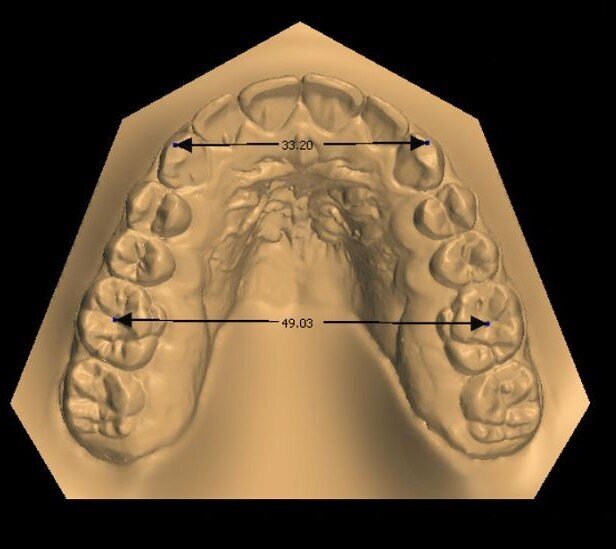

_Materiale e metodi Una paziente di sesso femminile di 11 anni, presenta all’esame clinico: dentizione permanente, palato di forma ogivale, discrepanza trasversale, affollamento e contrazione dell’arcata superiore, tipping vestibolare dei primi molari superiori, marcato affollamento dentale inferiore, tipping linguale degli elementi dentali postero-inferiori, proinclinazione vestibolare degli incisivi inferiori (Fig. 1). La paziente, inoltre, riferisce il menarca sei mesi prima dell’inizio della terapia. Per prima cosa è stato realizzato un setup digitale del risultato finale nell’arcata inferiore correggendo l’affollamento mediante espansione dei settori posteriori e minimizzando la proinclinazione degli incisivi. Utilizzando questo setup digitale come arcata guida, è risultata una discrepanza trasversale tra arcata inferiore e arcata superiore di circa 6 mm (Fig. 2).Richiesto l’esame CBCT, è stata valutata anche la morfologia della sutura palatina ed è risultata di tipo C secondo la classificazione di Angelieri et al11 (Fig. 3).

Fig. 2_Setup finale della correzione dell’arcata inferiore: nell’immagine è rappresentato in blu la posizione iniziale della dentatura, in bianco la posizione risultante dal setup. La lunghezza trasversale prevista a fine terapia sarà di 50 mm.

Fig. 6a_Misurazione distanza inter-molare e inter-canina a inizio terapia.